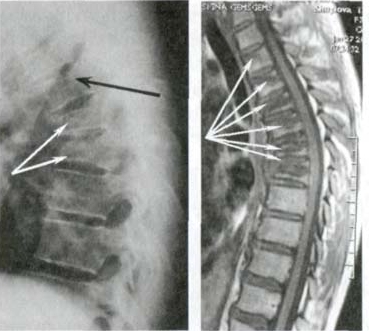

— Apakah Anda benar-benar berpikir bahwa pijat atau analgesik dapat mencegah kerusakan sendi dan tulang rawan? Itu adalah kesalahpahaman besar. Obat-obatan dari apotek tidak dapat meregenerasi jaringan, sementara bahan kimia yang terkandung di dalamnya justru merusak hati dan ginjal seiring waktu. Tubuh tidak dapat selamanya menanggung beban racun ini, dan alih-alih menyelesaikan masalah, Anda justru meracuni diri sendiri! Hal ini terutama berlaku untuk tulang belakang. Semua sendi mengalami keausan, tetapi pada tulang belakang, kurangnya ujung saraf dapat menyembunyikan perubahan yang berbahaya. Kompresi saraf skiatik akibat hernia adalah proses yang menyakitkan, awalnya menyebabkan nyeri ringan di punggung bawah, lalu menjalar ke kaki, menyebabkan kesemutan, mati rasa, dan akhirnya hilangnya fungsi kaki sepenuhnya. Kerusakan yang terus berkembang akan menyebabkan kelumpuhan pada bagian bawah tubuh, dan mengembalikan kendali atasnya menjadi hampir tidak mungkin. Lihat gambar ini. Ini adalah kondisi tulang belakang seseorang yang baru berusia 44 tahun, tetapi tampak seperti lansia. Dulu, kerusakan seperti ini hanya terjadi setelah usia 60 tahun, tetapi sekarang hal ini menjadi umum bagi mereka yang baru saja melewati usia 40 tahun. Kerusakan ini akan terus berkembang seiring bertambahnya usia, dan mengabaikannya berarti menempatkan diri dalam risiko kelumpuhan total!

Tulang belakang pasien berusia 44 tahun: semuanya dimulai dengan nyeri ringan, tetapi hanya dalam satu minggu muncul hernia, dan dalam dua minggu terjadi pergeseran tulang belakang, tekanan pada saraf, dan akhirnya—kursi roda.

Hernia cakram tulang belakang, kompresi saraf, kehilangan sensasi, dan kelumpuhan parsial pada kaki.

Setelah berkonsultasi dengan puluhan dokter, Nur Aisyah akhirnya menemui Dr. Siti Rahma dan berhasil mengalahkan penyakitnya. Pada tahun 2019, ia didiagnosis mengalami berbagai gangguan tulang belakang: hernia, kompresi saraf, dan deformasi tulang belakang. Dua tahun kemudian, sendi lututnya mulai mengalami degradasi, membuat setiap gerakan menjadi penderitaan. Ia tidak memiliki keluarga, tetapi ia tidak menyerah dan memutuskan untuk berjuang hingga akhir.